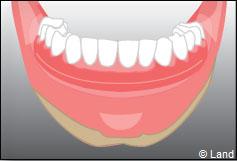

Exemple d’une réhabilitation complète implantaire

Situation clinique initiale